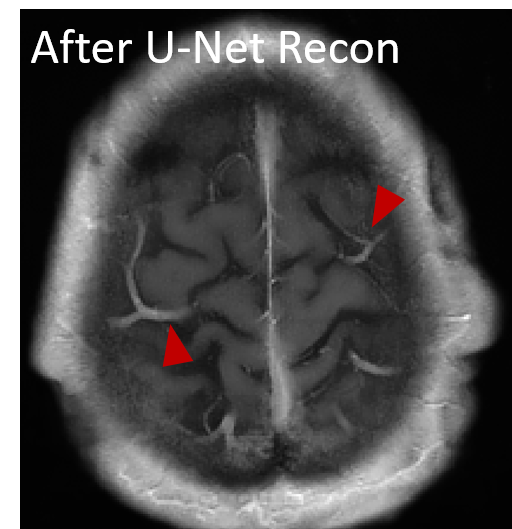

The reconstructed images from the learned trajectories using radial trajectory were demonstrated in Figure 4. These images were compared with the images directly reconstructed using fixed trajectory. The framework was slightly modified by removing the trajectory optimization network and only training the end-to-end reconstruction U-Net using the standard supervised learning approach. The qualitative evaluation of brain images proves the improved image reconstruction using our proposed method. As illustrated in Figure 4, the reconstructed images from learned trajectories are consistently better than those from the fixed trajectories for each type. More specifically, the learned radial trajectories provided improved reconstruction performance compared to their fixed counterparts in Figure 4 for the brain images at the AXT1POST sequence (More results in Appendix). Notably, the intermediate images directly obtained from the RSS reconstruction were shown at the top row of Figure 4 for the learned and fixed trajectories. It is evident that the learned trajectory can better remove structural and aliasing artifacts and provided more realistic image features and accurate image contrast than that of the fixed trajectory at the same level of acceleration, indicating the efficacy of the learning-based trajectory optimization.

The reconstructed images from the learned trajectories using Cartesian, and spiral trajectories were demonstrated in Figures 8, and 9, respectively. These images were compared with the images directly reconstructed using fixed trajectory. The framework was slightly modified by removing the trajectory optimization network and only training the end-to-end reconstruction U-Net using the standard supervised learning approach. The qualitative evaluation of knee and brain images proves the improved image reconstruction using our proposed method. As illustrated in Figures 8, and 9, the reconstructed images from learned trajectories are consistently better than those from the fixed trajectories for each type. More specifically, Figure 8 provides an example of a reconstructed knee image using a learned Cartesian trajectory at an acceleration factor (AF) of 4.4. This figure shows that the learned trajectory provides better image features, improved image sharpness, and more detail recovery due to their optimized k-space coverage. The learned Cartesian trajectory outperformed the regular Cartesian trajectory at the same acceleration rate. Likewise, the learned spiral trajectories provided improved reconstruction performance compared to their fixed counterparts in Figure 9 for the brain images at the AXT1 sequence. Notably, the intermediate images directly obtained from the RSS reconstruction were shown at the top row of Figures 8, and 9 for the learned and fixed trajectories. It is evident that the learned trajectory can better remove structural and aliasing artifacts and provided more realistic image features and accurate image contrast than that of the fixed trajectory at the same level of acceleration, indicating the efficacy of the learning-based trajectory optimization.